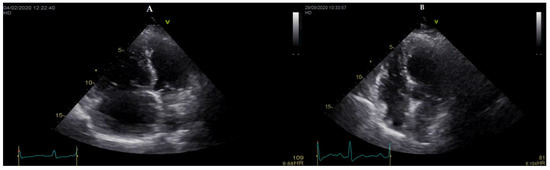

- D’Alto, M.; Badagliacca, R.; Argiento, P.; Romeo, E.; Farro, A.; Papa, S.; Sarubbi, B.; Russo, M.G.; Vizza, C.D.; Golino, P.; et al. Risk Reduction and Right Heart Reverse Remodeling by Upfront Triple Combination Therapy in Pulmonary Arterial Hypertension. Chest 2020, 157, 376–383. [Google Scholar] [CrossRef] [PubMed]